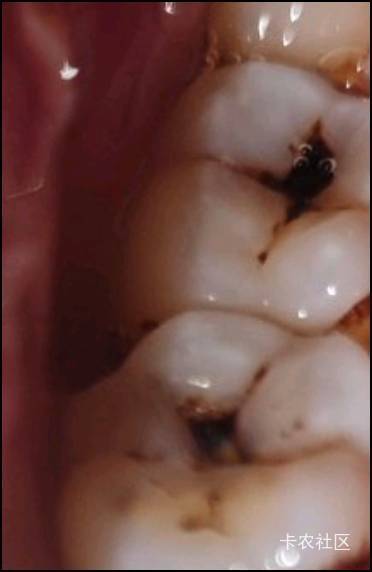

有一边有两个牙齿这样了,中间这么黑,另外一边就好好的

蛀牙  这黑的已经住了,要去把它磨掉,然后补一下才可以,要不然就会一直住下去。

快去补了,两个牙去三甲医院也就1000多,如果附近有诊所可以去诊所,诊所便宜点,你这个再不补,烂到牙神经只能做根管了,根管很贵,又废时间

早点去补,就几百的事。不然几千